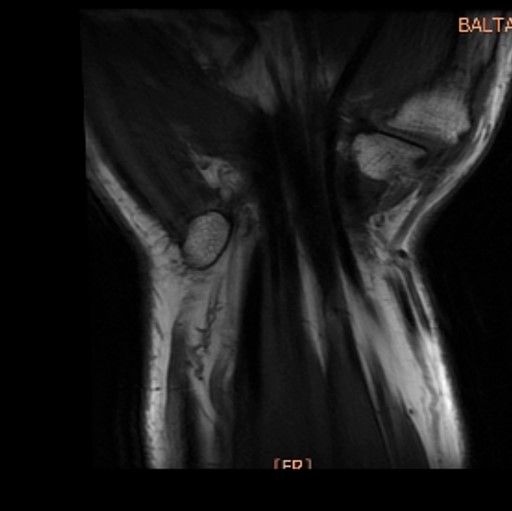

Case 20 - TFCC Rupture 38 yr, male, sweeper, right hand dominantRight wrist pain for seven months agoRepetative work-related trauma history in right wrist